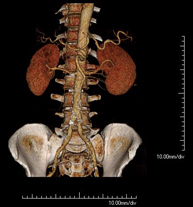

- Angio-TC aorta abdominal

Prueba diagnóstica no invasiva que consiste en el estudio de la arteria aorta abdominal obteniendo imágenes de alta definición anatómica mediante el empleo de un equipo de TC (Tomografía Computarizada) y de contraste yodado. La calidad de las imágenes permite realizar reconstrucciones en 2D y 3D gracias a estaciones de trabajo especializadas en el estudio arterial. Está indicado en aquellos pacientes con enfermedad vascular (aterosclerosis), en aneurismas de aorta, en pacientes con dolor abdominal de posible origen vascular, en estudios pre-quirúrgicos de lesiones adyacentes a la aorta abdominal como "mapa" vascular, etc. La información obtenida de forma no invasiva es indispensable para los pacientes que requieren tratamiento percutáneo o quirúrgico. En aquellos pacientes que solo requieren un seguimiento de las lesiones vasculares, esta técnica es la técnica no invasiva de elección junto con la angio-RM.

- Angio-TC arterias renales

Prueba diagnóstica no invasiva que consiste en el estudio de las arterias renales obteniendo imágenes de alta definición anatómica mediante el empleo de un equipo de TC (Tomografía Computarizada) y de contraste yodado. La calidad de las imágenes permite realizar reconstrucciones en 2D y 3D gracias a estaciones de trabajo especializadas en el estudio arterial. Esta prueba está indicada, por ejemplo, en aquellos pacientes que sufren de HTA refractaria al tratamiento, en pacientes con lesiones renales para tener un mapa "vascular" pre-quirúrgico, etc.